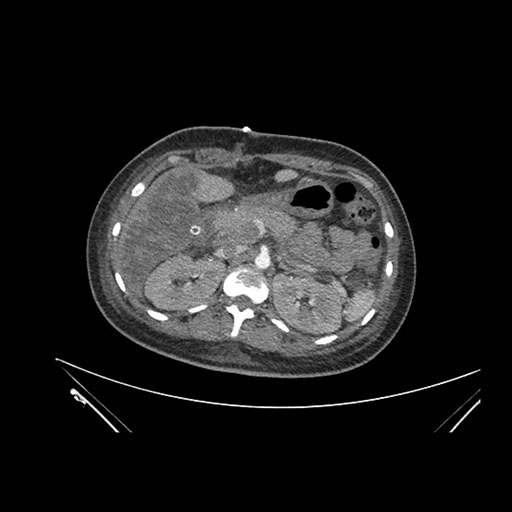

Axial Venous

Imaging analysis

Based on initial findings, which issue(s) would you be most concerned about?